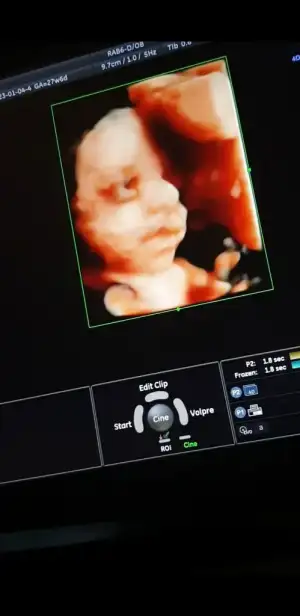

Kızlar iyi akşamlar, biraz önce kontrolden geldim, sat a göre 27+6 ama ultrasonda 27+4 çıktı, bebeğim 1120 gr - 36 cm olmuş🥰 rahim ağzı uzunluğum 4 cm üzeri çıktı.

Herşey yolunda gidiyor çok şükür, inşallah hiçbir problem çıkmadan hepimiz sağlıcakla doğururuz🙏

Video çekmiştim ondan kareler aldım😍

Her dururuşu bebeği değiştiriyor.

Screenshot_20230104-182322_Photos.jpg Screenshot_20230104-182558_Photos.jpg Screenshot_20230104-181937_Photos.jpg